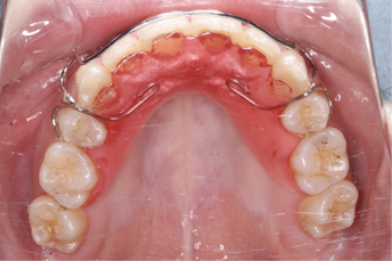

上顎の裏側(舌側)Fixワイヤー固定